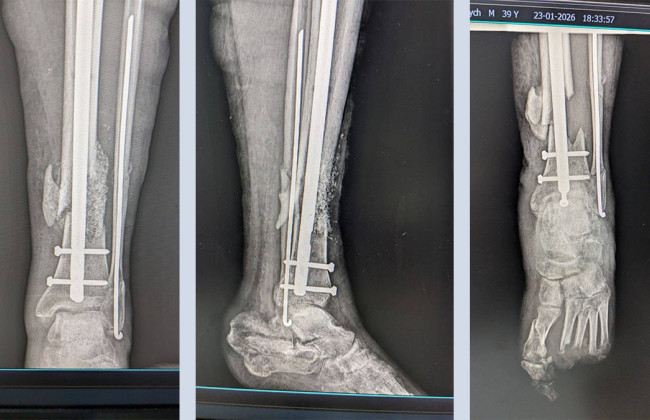

За його словами, медики виконали складне реконструктивне втручання, поєднавши аутокісткову пластику (використання власної кістки пацієнта) з біоактивним склом — сучасним матеріалом, який стимулює регенерацію кісткової тканини.

Біоактивне скло не лише заповнює дефект, а й сприяє остеоінтеграції та формуванню нової кістки, знижуючи ризик ускладнень і покращуючи функціональні результати лікування.